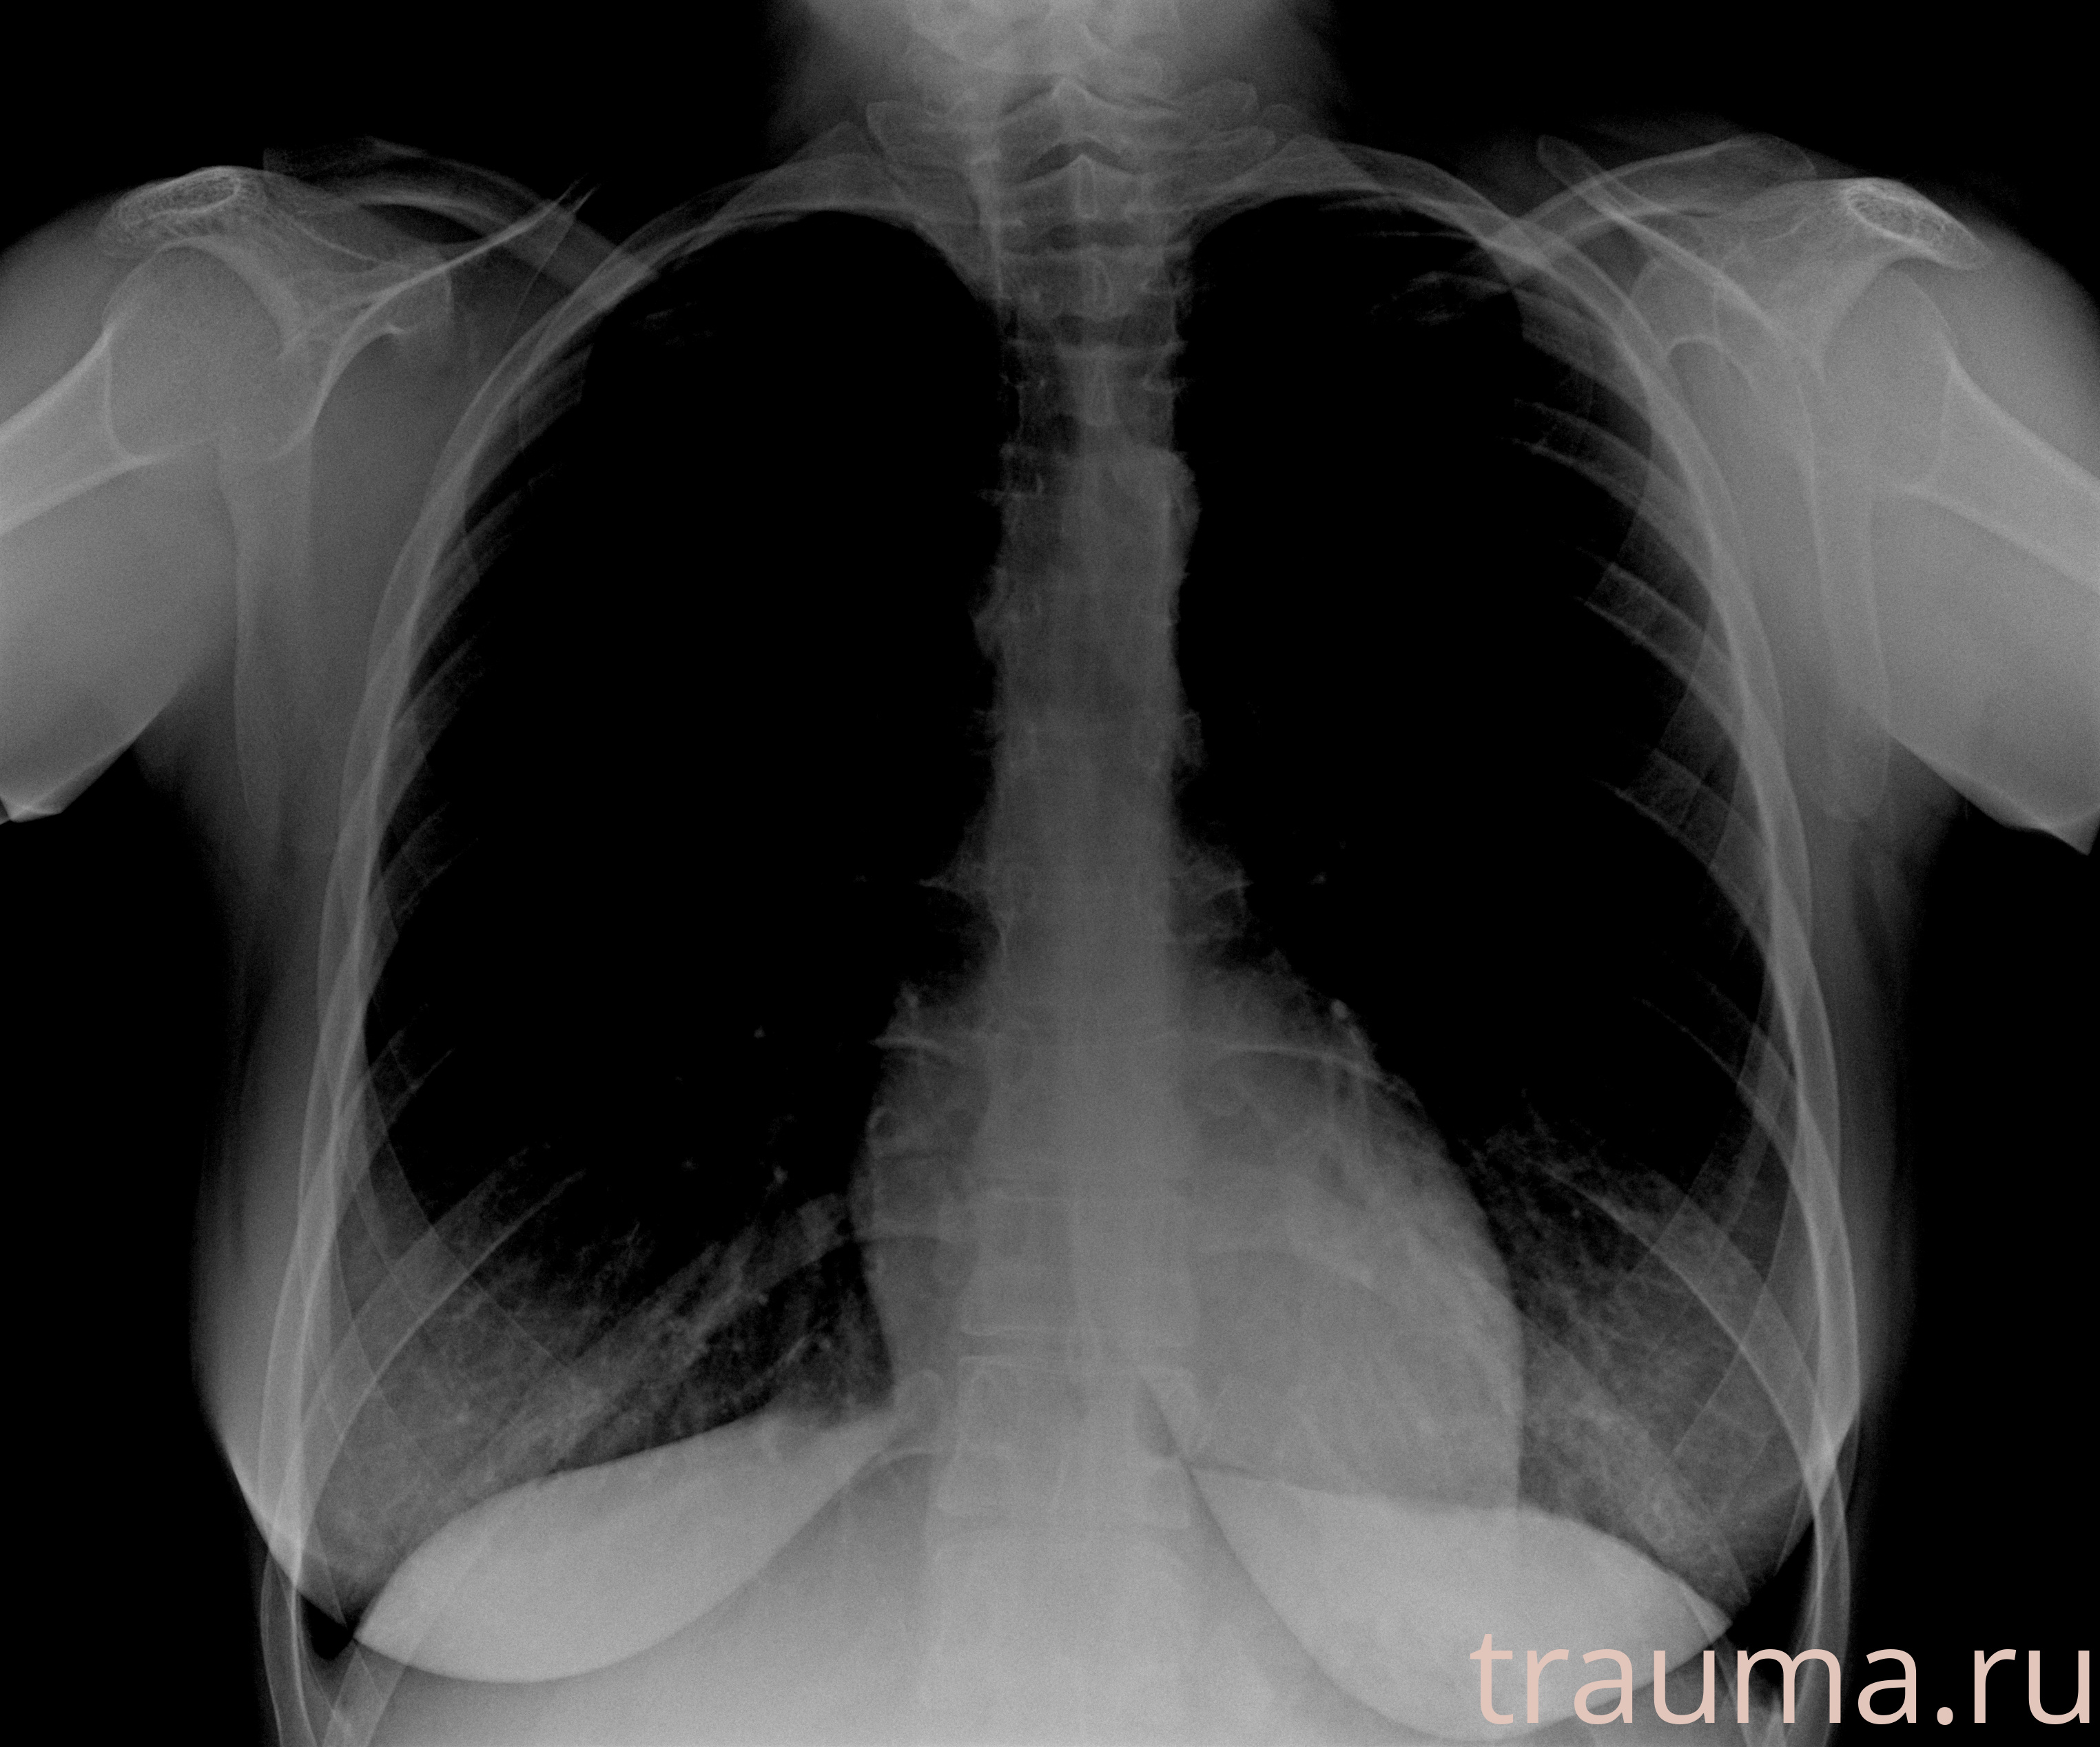

Рентгенограммы

Рентген на дому: по вашему адресу приезжает врач-рентгенолог, травматолог-ортопед с мобильным рентгеновским аппаратом, проводит диагностику травмы или заболевания, делает необходимые рентгенограммы, дает рекомендации по дальнейшему лечению. Получить качественные снимки в домашних условиях возможно благодаря уникальной методике, разработанной МосРентген Центром для института  Склифосовского